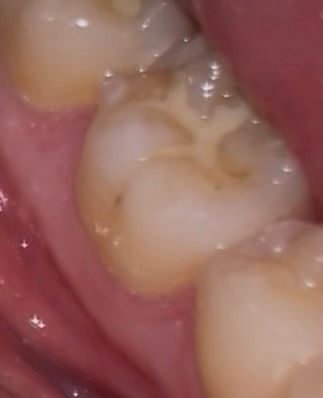

이정도 치아 깨진거 치료 받아야할까요? +충치

딱딱한거 씹다가 깨졌는데

가끔 뜨거운거 먹었을때시큰거리는 정도고

일상생활할때 불편한건 없습니다

1. 깨진거 치료 받아야할까요?

2. 저정도 깨짐은 어떻게 치료하나요? 아플까요?

2. 옆면에 있는 충치 상태도 좀 봐주세요 ㅠㅠ

추가적인 파절을 예방하기 위해서는 치료는 받으시는 게 좋겠고 인레이 해야할 것 같습니다.

사진으로 봤을 경우에 치아가 깨진 것보다 부분 부분 충치가 보이고 있습니다. 충치가 있는 부분엔 이물질이 남아 있게 되어 충치가 진행될 수 있으니 충치가 있는 부분은 치료를 해주는 것이 좋습니다.

깨진 정도가 크진 않으나 한번 깨졌던 치아는 그 부위가 씹을때 힘이 강하게 가해진다는 것이므로 또 추가적으로 깨질 우려가 큽니다. 전반적으로 상태 보고 레진으로 떼우거나 아니면 크라운을 씌워주면 좋을 것 같습니다.

옆면 충치 큰 편은 아닙니다.